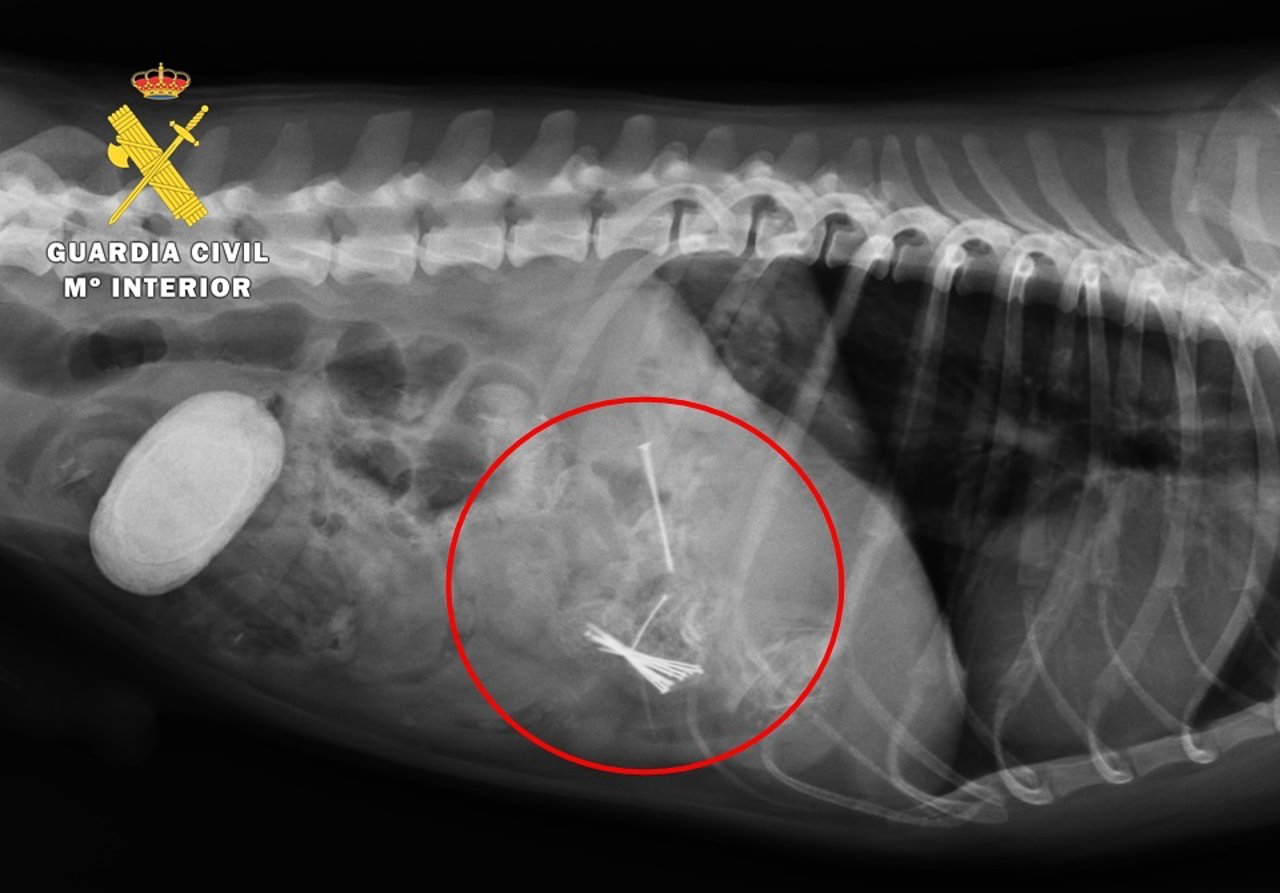

Identificado por dejar carne con alfileres que lesionó a un perro

Radiografía del animal

Al observar su dueño que el animal no se encontraba bien le llevó rápidamente a una clínica, donde tras varias radiografías se observaron varios cuerpos metálicos en el estómago del perro. El veterinario le operó de urgencia y extrajo una pieza de carne que enmascaraba 18 alfileres metálicos.